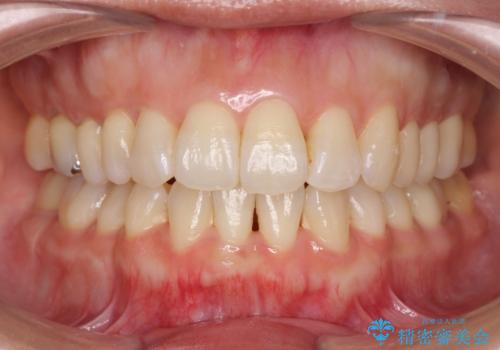

治療に制約がある場合でも、現実的な治療ゴールを設定することで機能的・審美的な歯並びを手に入れることができました。

職業柄ワイヤー矯正ができない、マウスピース矯正で行う八重歯抜歯症例

- 2年6ヶ月